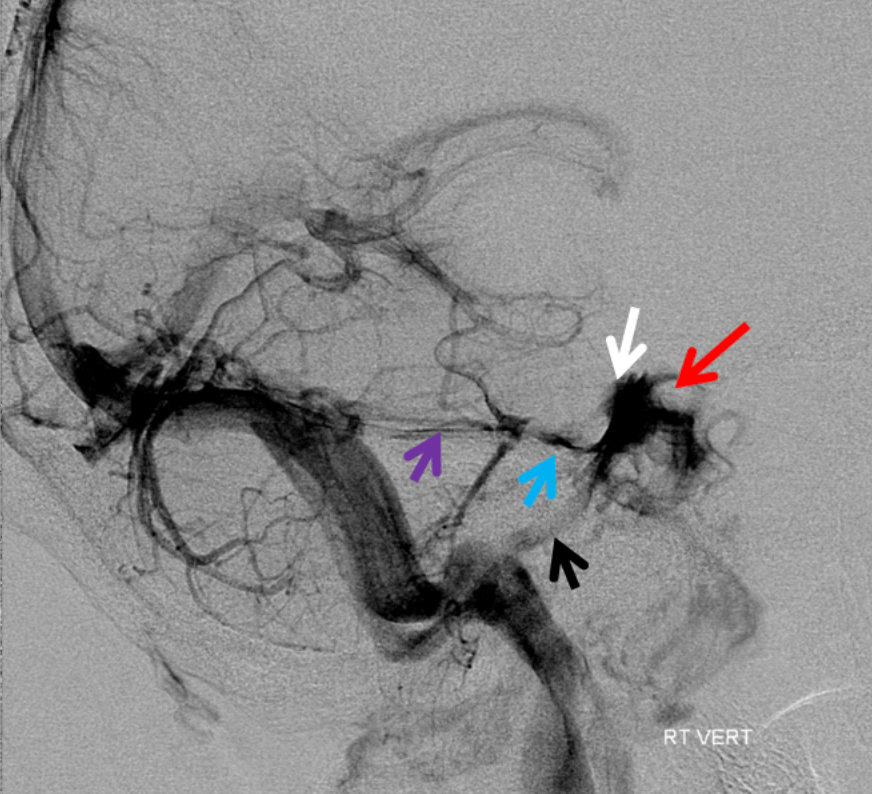

On the venous phase of this lateral R vert injection, name the purple arrow:

Superior Petrosal Sinus

petrosal veins (blue), cavernous sinuses (white), inferior petrosal sinus (black), silhouette of the ICA (red).